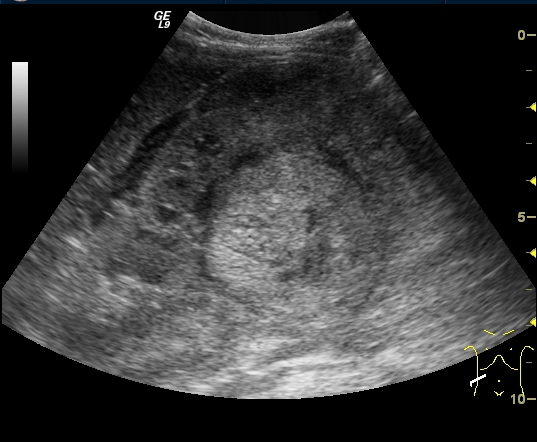

Image

27. A solid, echogenic mass arising from the right kidney. Wilms tumor. Abdominal US.